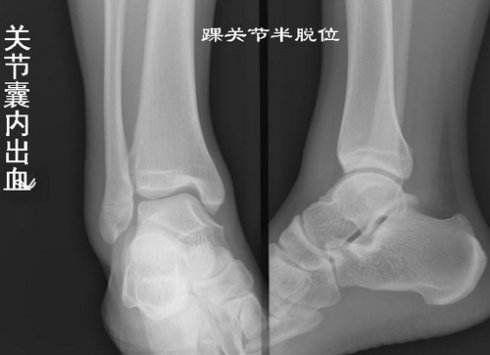

踝关节和足部的骨折,脱位是骨科常见的损伤,踝关节的关节面比髋、膝关节的关节面小,担负但的重量与活动却很大,故易发生损伤。占全身骨折的3.83%,多见于青少年。下面我们来看看踝部骨折饮食注意一些什么吧?